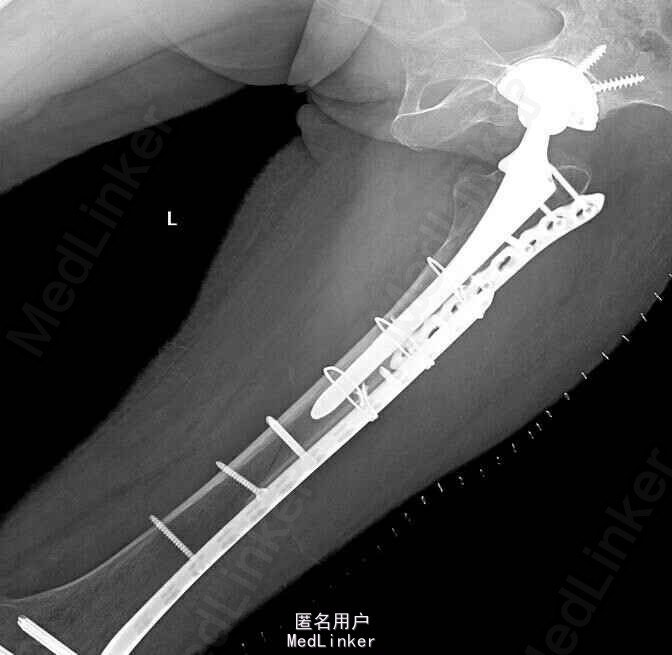

行左股骨假体周围骨折切开复位内固定术

术后恢复良好